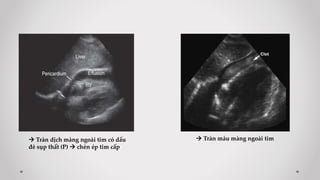

 Mặt cắt 1: dưới mỏm mũi kiếm xương ức

Trả lời các câu hỏi:

- Tràn dịch màng ngoài tim?

- Có tổn thương gan Trái?

- Đánh giá IVC

 Tràn dịch màng ngoài tim có dấu

đè sụp thất (P)  chèn ép tim cấp

 Tràn máu màng ngoài tim